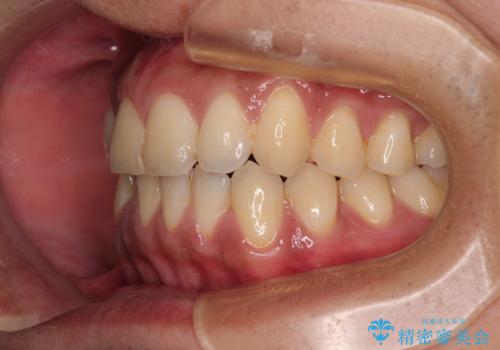

診察したところ、上下顎前歯部に軽度の叢生(ガタつき)が認められます。

目立たない装置を希望されたのでインビザライン ライトパッケージで治療を行うことになりました。